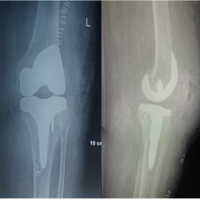

MRI showed marrow edema with enhancement in the distal tibia and talus and calcaneum with multiple subchondral cysts with diffuse cortical erosions adjacent to the articular surfaces (Fig. 3).